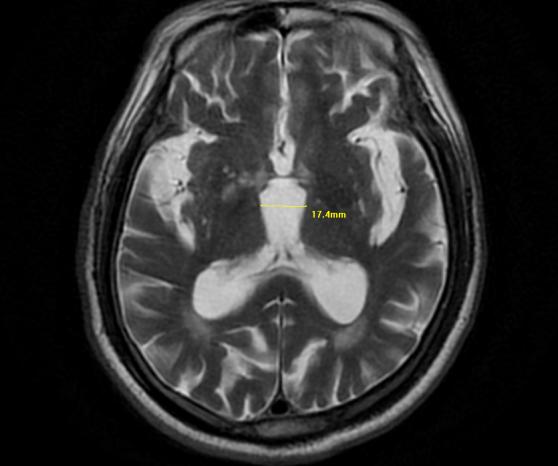

随后,脑部核磁共振影像证实了诊断:患者中脑明显萎缩,侧影形似一只“蜂鸟”。这正是PSP的特征性表现——“蜂鸟征”。该病目前尚无根治方法,主要以对症支持、康复护理为主,但明确诊断能帮助患者及家属停止盲目求医,进行针对性康复与管理,预防跌倒骨折、吸入性肺炎等并发症,有效提升生活质量。